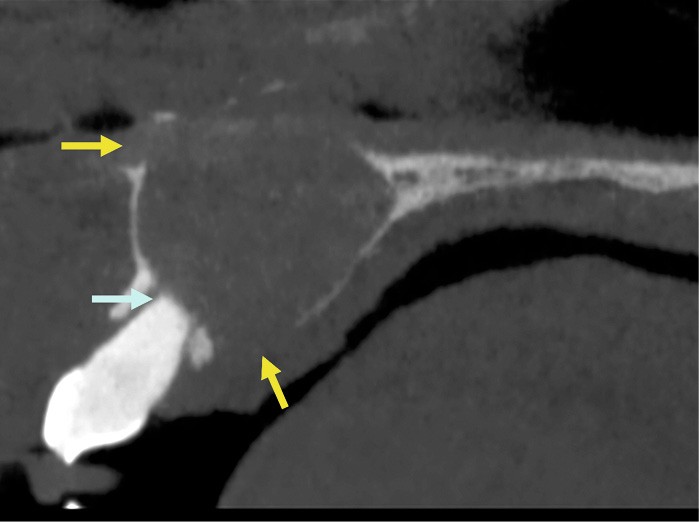

- Plus rarement, extension latérale jusqu’aux prémolaires de façon asymétrique (fig. 5).